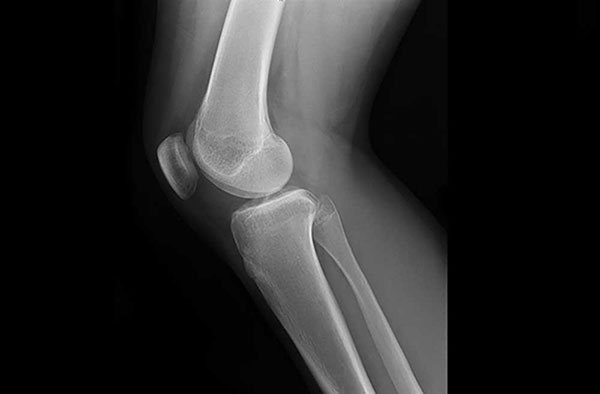

Hình ảnh bên trong khớp gối giúp chẩn đoán nguyên nhân lỏng khớp gối

Hình ảnh chụp X-quang hoặc chụp cộng hưởng từ MRI ghi lại hiện trạng cấu trúc khớp gối một cách rõ ràng giúp bác sĩ nhận định chính xác nguyên nhân làm khớp gối mất ổn định. Ngoài ra, thông tin về chấn thương xảy ra ở khớp đầu gối trước đó hay tiền sử bệnh lý (nếu có) mà bạn cung cấp sẽ rất hữu ích cho bác sĩ trong việc đánh giá những yếu tố có thể là nguy cơ làm tăng nặng mức độ lỏng lẻo và bất ổn của đầu gối.